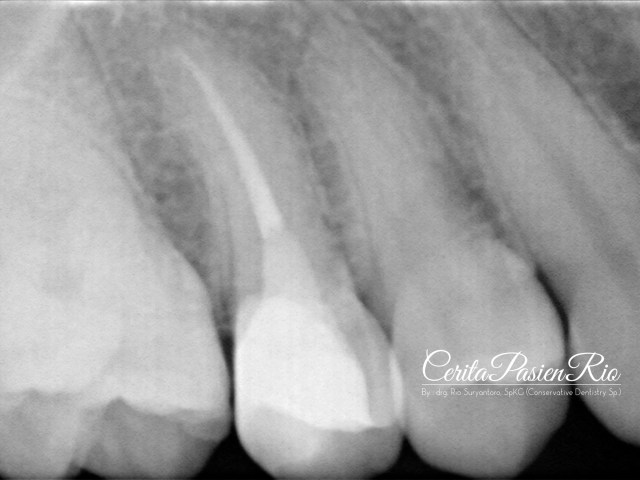

gambar 21. evaluasi radiograf pasca pengisian saluran akar. tampak integrasi tepi tambalan resin komposit kelas 2 yang baik, coronal seal yang juga beradaptasi yang baik dengan gutta percha dan gigi.